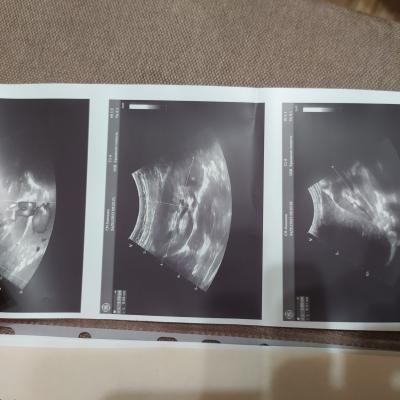

Добрый день! Прошу проконсультировать по поводу анализа мочи и УЗИ. В анализе мочи повышены соли и эритроциты, УЗИ показало расширение лоханки. Чувствую себя нормально, жалоб нет. В детстве переболела пиелонефритом. Результаты анализов прикладываю. Спасибо.